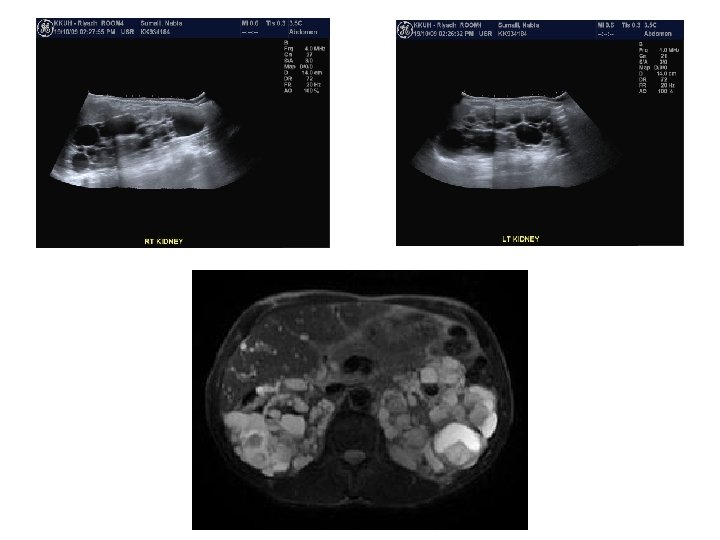

Case (3) • Elderly male patient with recurrent urinary tract infections.